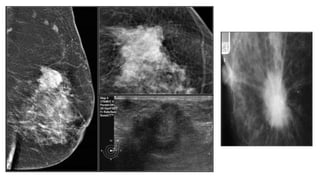

● Contrast was injected

into the node and a

repeated mammogram

was performed.

● Here we have proof

that the mass is

node, since the

● Contrast wasinjected into the node and a repeated mammogram was performed. ● Here we have proof that the mass is caused by an intramammary lymph node, since the mammographic mass contains the contrast

• #43 They are of a patient with a new lesion found at screening. With ultrasound an intramammary lymph node was found, but we weren't sure whether this was the same as the mass on the mammogram.

• #50 This patient presented with a mass on the mammogram at screening, which was assigned as BI-RADS 0 (needs additional imaging evaluation). Additional ultrasound demonstrated that the mass was caused by an intramammary lymph node. The final assessment is BI-RADS 2 (benign finding).